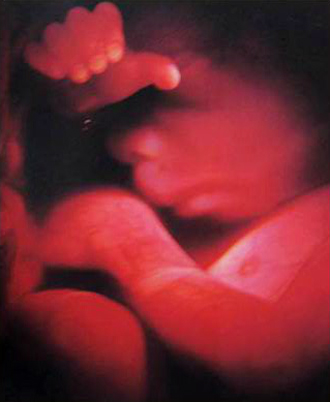

- 임신 증상진단

- 뚜렷한 임신증상이 없을 수 있습니다.

증상:입덧, 피로, 빈뇨, 두통 등 - 임신확인 검사

배란일로 보터 일주일 이후가 되면 임신테스트기로 임신사실이 확인됩니다.